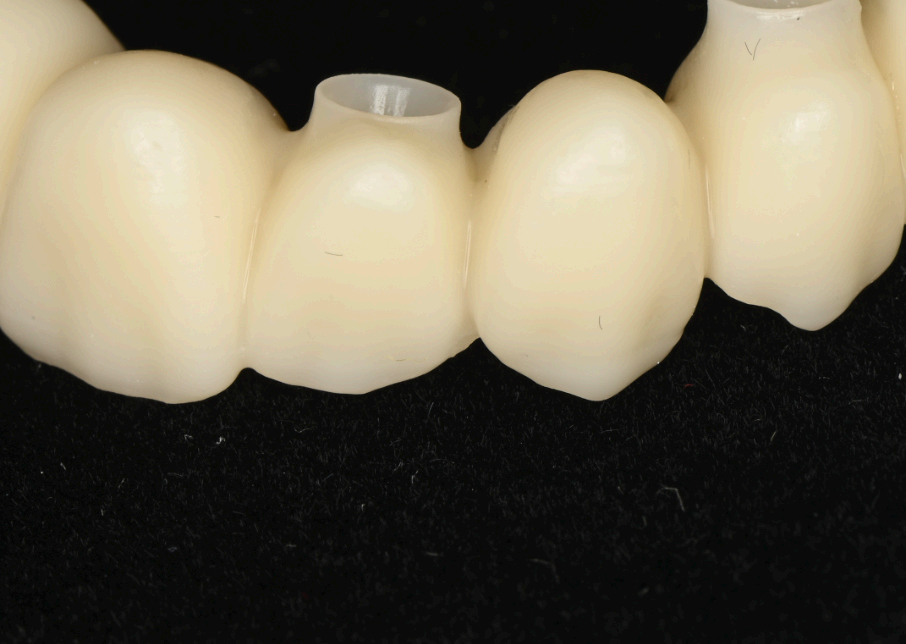

The fnal prosthesis was designed as a hybrid structure, combining a translucent zirconia framework with a metallic iBar for strength and durability (Fig. 7.2, 7.3). The iBar was modeled in Blender4Dental, optimizing its geometry to distribute occlusal forces across the six implants (Fig. 7.4). The zirconia component was milled to achieve a natural translucency, mimicking the optical properties of natural teeth. After fabrication, the prosthesis was inserted, secured to the MUAs via screw retention, and adjusted to ensure proper occlusion and patient comfort (Fig. 7.1). The fnal design adhered to FP1 principles, replacing only the dental crowns while harmonizing with the scalloped gingival profle established during healing.

Group 7: Final Prosthesis Fig. 7.1: Final FP1 prosthesis in situ, showcasing aesthetic gingival integration. Fig. 7.2: Translucent zirconia hybrid prosthesis prior to insertion. Fig. 7.3: Zirconia prosthesis with embedded iBar pre-insertion. Fig. 7.4: iBar design process in Blender4Dental.

At three months post-surgery, the soft tissues exhibited a mature, festooned contour that enhanced the aesthetic integration of the prosthesis (Fig. 6.1, 6.2). The refned provisional had successfully guided this outcome, with the gingival margins aligning seamlessly with the prosthetic teeth (Fig. 6.3–6.6). The fnal zirconia-iBar prosthesis demonstrated excellent stability, with no signs of mechanical complications or peri-implant infammation (Fig. 7.1). Aesthetically, the restoration fulflled the patient’s expectations, achieving a natural smile with balanced proportions and a lifelike gingival appearance. Functionally, the patient reported full satisfaction with mastication and speech, indicating a successful rehabilitation.

The choice of a zirconia-iBar hybrid for the fnal prosthesis balanced aesthetics and strength, leveraging the iBar’s rigidity to support the arch while allowing the zirconia to provide a natural translucency. The use of Blender4Dental for iBar design exemplifes the fexibility of modern CAD software, enabling precise customization that aligns with the patient’s anatomy and occlusal demands. Collectively, these elements—photogrammetry, digital planning, immediate loading, and advanced materials—illustrate a cohesive workfow that maximizes predictability and patient satisfaction.